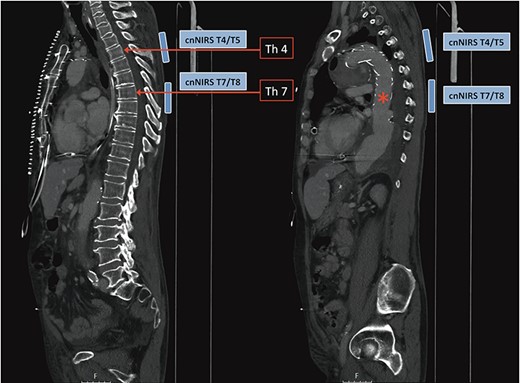

A 66-year-old patient suffering from a degenerative aortic aneurysm involving the ascending aorta, the arch and the thoracoabdominal aorta was scheduled for ascending aortic and extended aortic arch replacement with a frozen elephant trunk (fET) in preparation for a second-stage thoracic endovascular aortic repair. The preoperative computed tomography scan revealed a maximum diameter of 7 cm of a berry-like sack connected to the transverse arch (Fig. 1). On echocardiography, the aortic valve was competent.

Preoperative CT reconstruction of the ascending and arch aneurysm.